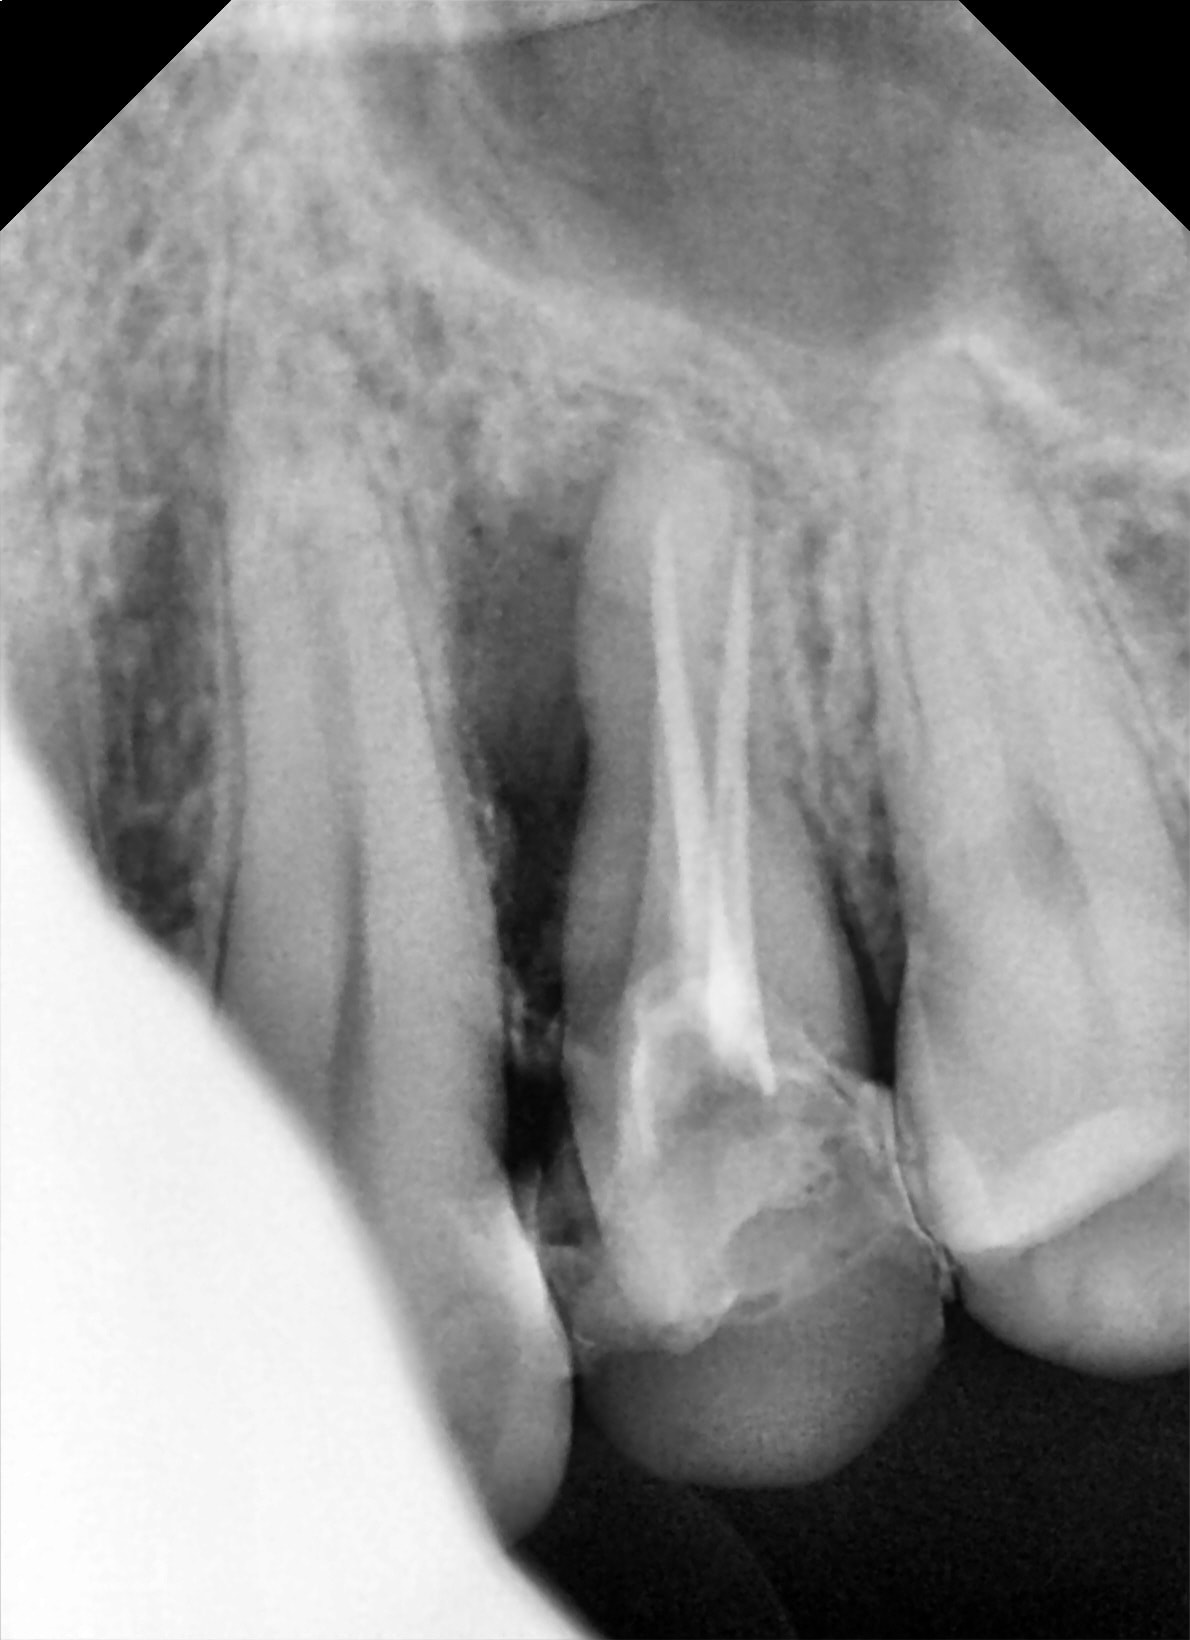

CasKiPu N°1:

Une 24 qui c'est fait mesialo-troué un troisième virtuel il y a un environ an chez un patient en pleine forme. Résine une dent ($$$) ou cobaye ? il dit cobaye :)

stabilité nickel , maxi patate en mesial, exo difficile car racine en forme de boursouflure coalesco-divergente.

Je dilate, ça sort.

visuellement c'est la merde:

- un cône de gutta

- une coulure de ce qui semble être un ciment composite

- un bouchon de MTA-like.

Coup de bistrac sur la racine, je gratoulle une couche de MTA et vu la coulure de compo je curète léger (ce que je ne fait jamais d'habitude) voir si il n'y aurai pas du rab.

J'enfourne ensuite au plus vite, deux point de superbond sur les adjacente (alvéole dilatée), un doliprane, ordo pour un cierge à la grotte et adishatz.

presque 2 semaines après.

Fistule : y'a pu

mes points de colle ont partiellement foutu le camp mais mobilité normale.

plus de douleur.

à suivre. J'y crois moyen mais pour l'instant ça sent bon...